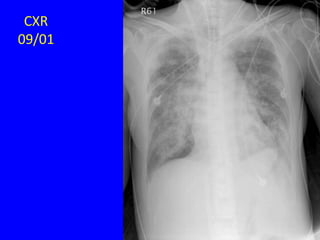

CXR

09/01